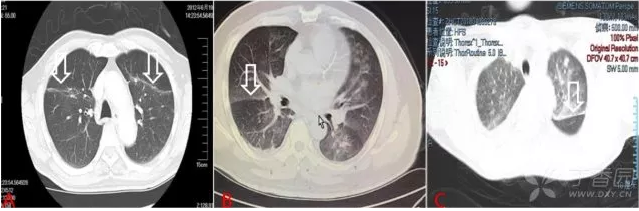

1. 肺纹理重新分布

QQ浏览器截图20200505212350.png

图 1 心源性肺水肿典型表现:肺纹理重新分布

图 1A 为正常胸片,B 为一心衰患者胸片。图 1B 为典型间质性肺水肿表现:肺上野和外带肺纹理显著增多,并可见 Kerley 线(细白箭指示)。

图 1D 患者为急性左心衰患者,与治疗后症状缓解时相比(图 1C),其近胸膜处肺纹理显著增多,左肺可见弥漫性渗出,并可见双侧胸腔积液。

在 X 片还是 CT 上,我们都可以看到心力衰竭引起肺静脉压力增高典型表现。

(1)肺纹理重新分布

生理状态下,由于重力原因,中下肺静脉中的血液会明显多于上肺,影像表现为:肺纹理以中下肺明显,上肺较为稀疏。

心衰发生时,由于肺动脉压力升高,肺淤血加重,肺纹理会重新分布,表现为:上中下肺纹理分布无明显差异,上肺纹理较无心衰时明显增多。

(2)上肺、肺外带纹理增多且较模糊

由于肺静脉充盈更明显,本来肺纹理显示不清楚的肺外带纹理也会增多。而且,由于肺毛细血管静水压增高,液体向肺泡渗出增加,肺纹理也会变得模糊。